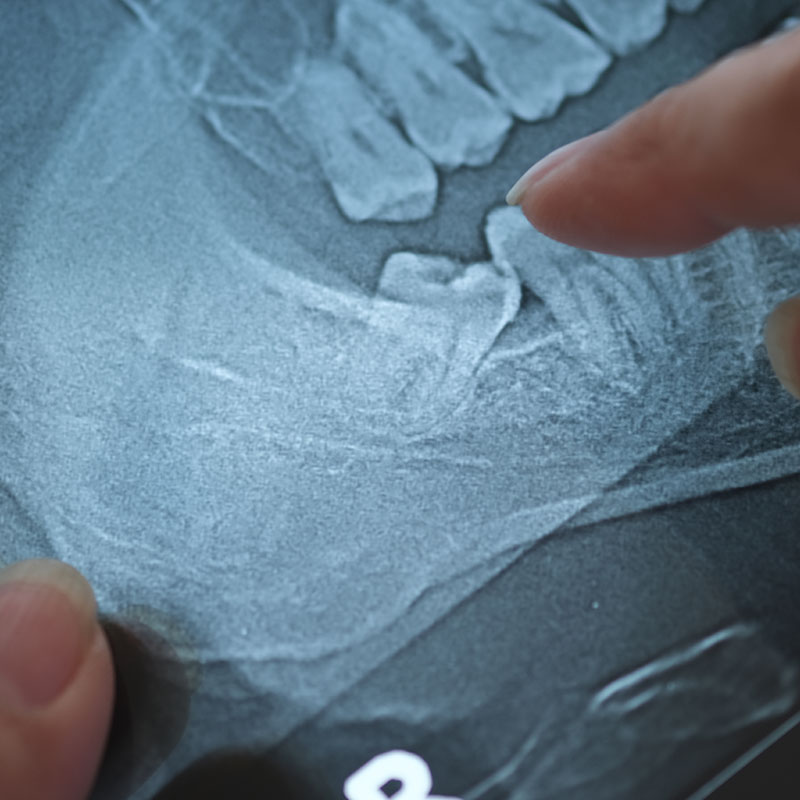

Tandlægen tager et røntgenbillede af visdomstanden for at se, hvordan tanden og roden ligger i kæben. Uanset om tanden skal trækkes eller opereres ud, bliver man lokalbedøvet. Derfor er det relativt smertefrit at få fjernet visdomstanden. Da man er ved fuld bevidsthed, kan man til gengæld både høre og fornemme, at der bliver arbejdet i ens mund. Man skal ikke være fastende før operationen. Faktisk kan man blive utilpas på grund af lavt blodsukker, hvis man møder fastende.

Hos nogle er der en lille risiko for beskadigelse af følenerven, som kan ligge tæt på visdomstandens rod. Det er blandt andet derfor vigtigt, at der tages et godt røntgenbillede inden fjernelse af visdomstanden. Du kan også få mere information om implantat behandling eller kirurgi i Silkeborg.